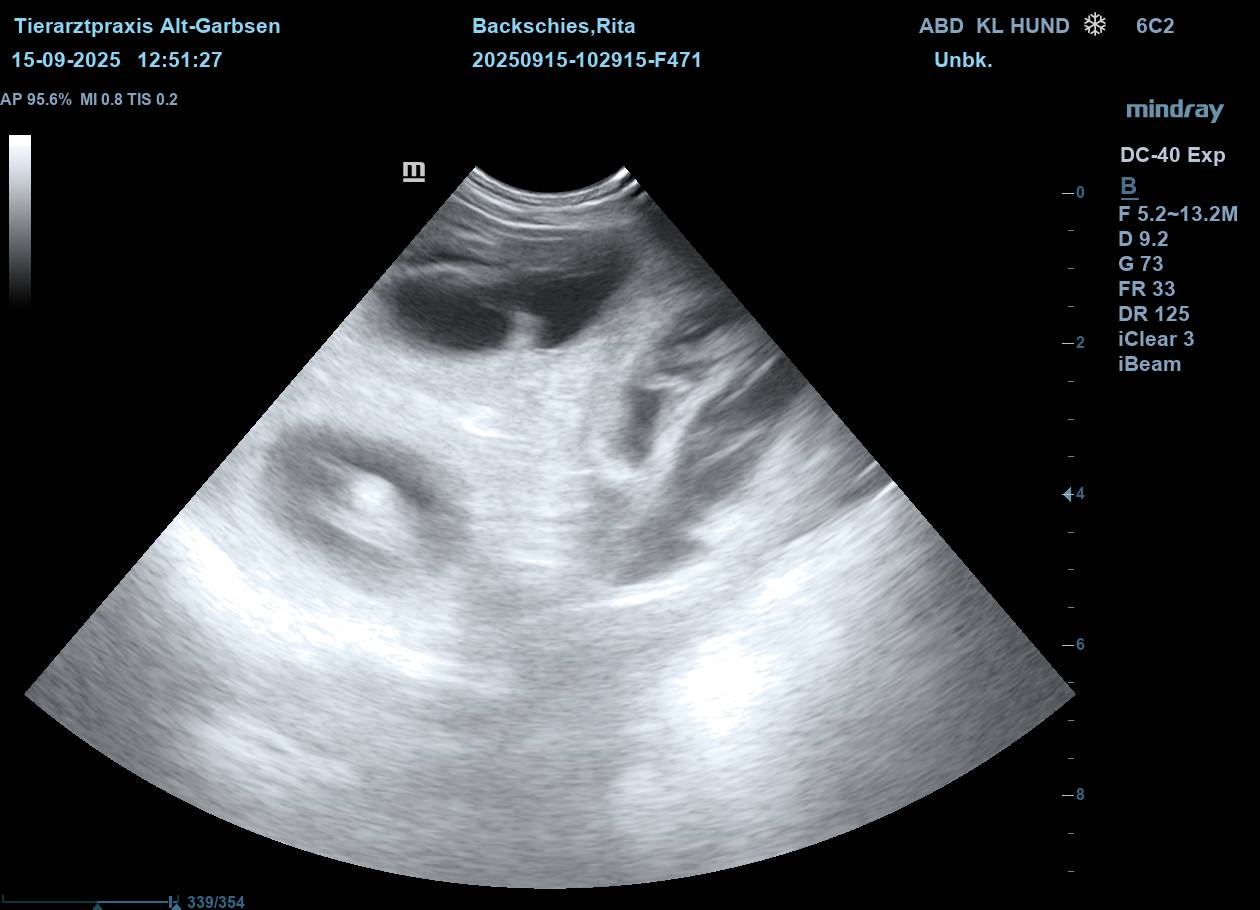

| Mo, 15.09.2025 | Es bahnt sich was an… der S-Wurf aus dem Zwinger Vom Lahberg FCI ist in die Produktion gegangen. Die Verpaarung am 17.08.2025 von Julissa Lisant Ingrid für Wambachtal „Rita“ und Kuddel vom Lahberg FCI war erfolgreich.🌿 Wir dürfen gespannt sein. In den nächsten Wochen werden wir dann Bilder vom wachsenden Babybauch posten. ![]() ![]() ![]() ![]() ![]() Jetzt heißt es mal wieder abwarten, beobachten, Däumchen drehen und hoffentlich bald freuen. |